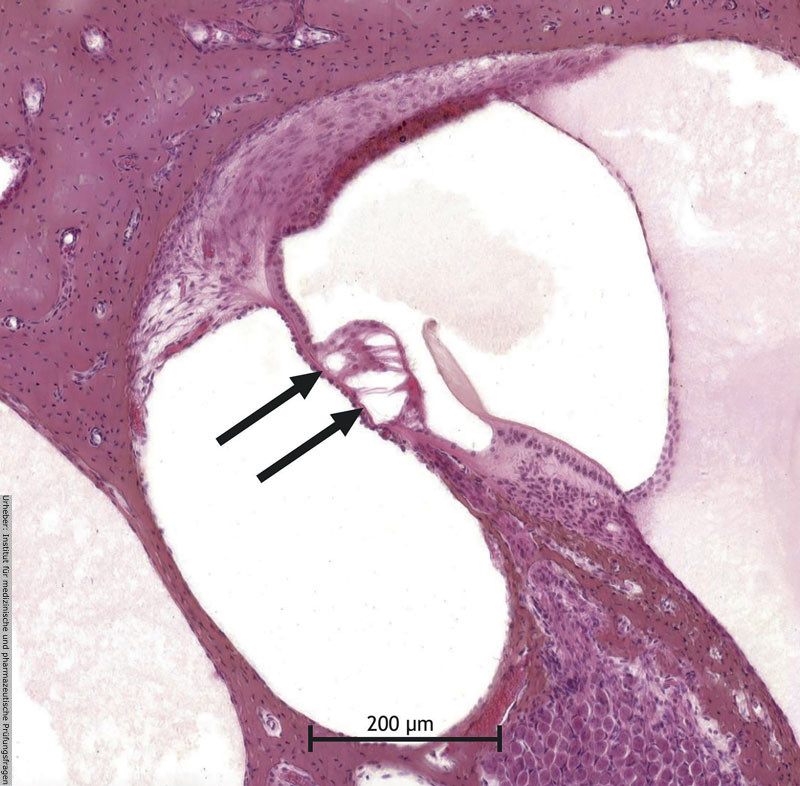

2.33 Das bereitgestellte Bild stellt einen histologischen Schnitt durch das Innenohr dar.

Um welche anatomische Struktur handelt es sich bei der mit den Pfeilen markierten Region?

- (A) Reissner-Membran

- (B) Tektorialmembran

- (C) Basilarmembran

- (D) Lig. spirale

- (E) Stria vascularis